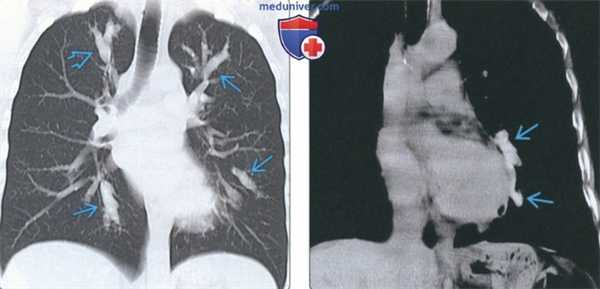

(Слева) На аксиальной КТ без КУ у женщины 61 года с острой идиопатической эозинофильной пневмонией определяются диффузные участки «матового стекла» на фоне утолщения междольковых перегородок и внутридольковых тяжей. Это т.н. картина «сумасшедшей исчерченности».

(Справа) На корональной КТ без КУ у этой же пациентки определяются диффузные двусторонние участки «матового стекла». Острая эозинофильная пневмония характеризуется быстрым возникновением дыхательной недостаточности, лихорадки и эозинофилии, и связана с недавним началом курения или вдыханием пыли во время терактов во Всемирном Торговом Центре.

• ОЭП:

о «Матовое стекло» (100%), картина «сумасшедшей исчерченности», «мозаичная» картина

о Утолщение междольковых перегородок в отсутствие узлов (90%)

о Утолщение бронховаскулярных пучков (66%)

о Консолидация (55%)

о Центрилобулярные очаги с нечеткими границами (30%)